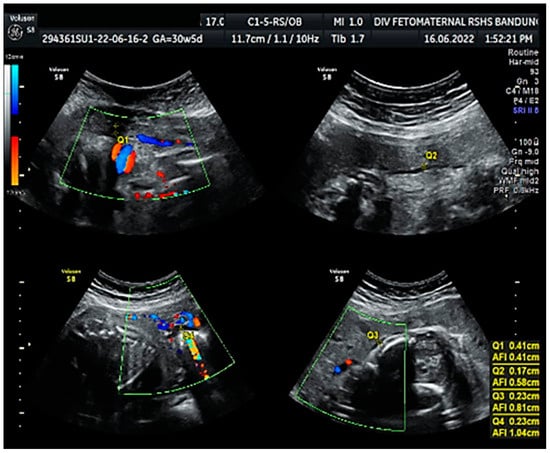

Color Doppler examination of the MCA revealed a peak systolic velocity of 42.33 cm/s, which is 1.045 times the median (the normal range is 40.5 cm/s for this gestational age), with persistent reversed end diastolic flow (Figure 2). The umbilical artery pulsatility index (PI) was 0.99, and RI was 0.63, with an S/D ratio of 2.71. There was notching on the right uterine artery, with a PI of 2.11. Notching was also found on the left uterine artery, with a PI of 1.58 (Figure 3). Laboratory results were within a normal range.

The Doppler examination also revealed a notching of the right and left uterine arteries, which is a marker of spiral artery remodeling failure, causing early-onset severe preeclampsia [11,12]. In this case, inadequate early prevention worsened the patient’s condition, leading to severe preeclampsia. The pregnancy did not present with hydrocephalus, cerebral hemorrhage, or mechanical compression of the fetal head. Another anatomical abnormality cannot be assessed intrauterine, nor seen after delivery. We did not perform a postnatal examination to exclude any internal neonatal anatomy abnormalities.

Figure 3. Notching on right and left uterine artery Doppler.